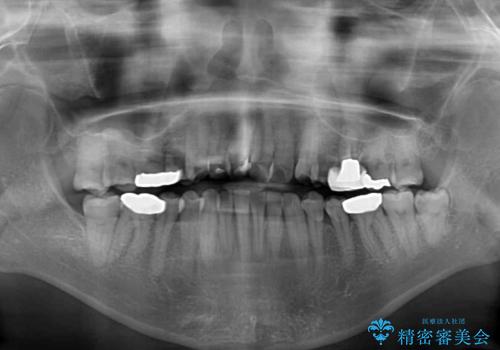

- かつて抜歯矯正を行ったものの、後戻りをしてしまったとのことで来院された患者様です。

上顎前歯が前突し、隣の歯が裏側に移動してきている状態でした。

飲み込みの状態を確認したところ、舌の突出癖が認められたため、それによる後戻りの可能性が高いと考え、舌のトレーニングを指導しました。